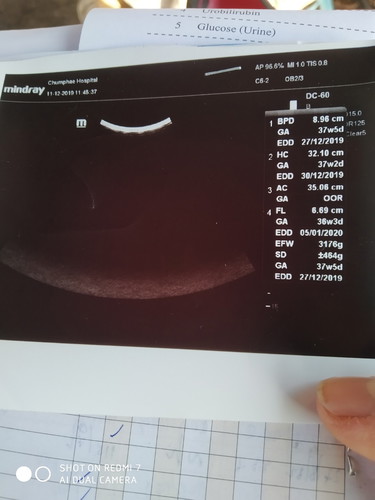

อยากทราบว่าน้ำลูกเท่าไร

มีแม่คนไหนพอจะอธิบายตามภาพอัลต้าซาวด์ได้บ้างค่ะ

น้ำหนัก3176g.ค่ะ